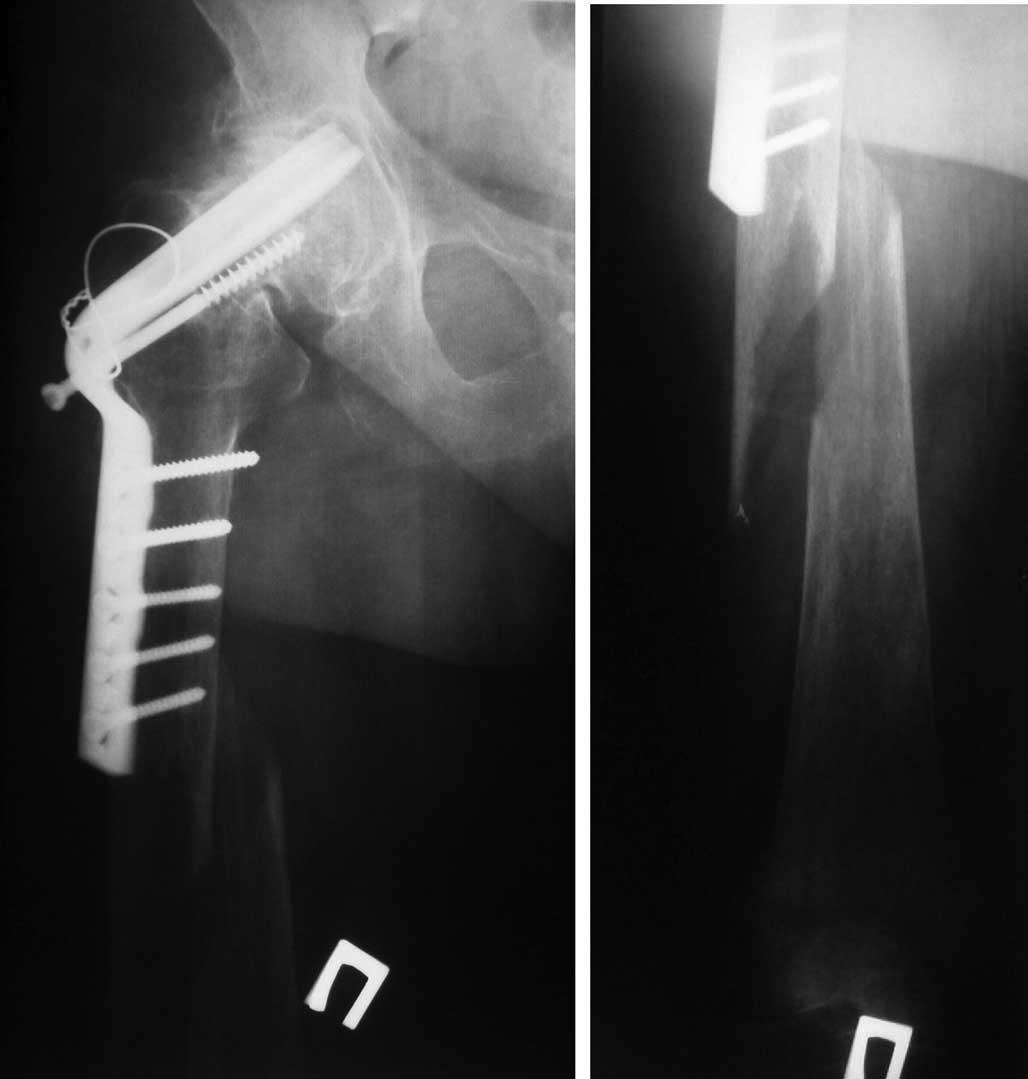

Женщина 86 лет, 7 лет назад корригирующая остеотомия по Mc Murray по поводу ложного сустава шейки бедра. Двигательная активность в пределах квартиры, передвигалась с дополнительной опорой и обслуживала себя, все это время к врачу не обращалась.

Упала по неосторожности, доставлена СМП. Проводится склетное вытяжение. Планируем - имеющийся фиксатор не трогать, т.к. он участвовал в опорности этой конечности (7 лет пациентку устраивал) и у нас нет полной уверенности в сращении ложного сустава.

Учитывая проблемный соматический статус : тучность , ХОБЛ; оперативное вмешательство планируем с минимальной агрессией, не вмешиваясь на винтообразный прелом, растянуть на дистракционной приставке по методике LIIS, накостная фиксация LSP 5.0 мм, располагая фиксатор по передне-боковой поверхности бедра.С удовольствием выслушаем советы по лечению этого перелома.

Уважемые колеги,на мой взгляд пластину стоит удалить (пенетрация клинка в сустав, вылезший компрессирующий винт, резорбция вокруг клинка).

В данном случае, с моей точки зрения, для выбора дальнейшей тактики лечения чрезвычайно важно установить факт сращения перелома шейки бедренной кости. Можно было бы получить дополнительную информацию о степени сращения, выполнив РКТ тазобедренного сустава. Если сращение перелома шейки бедренной кости не достигнуто, то наиболее приемлемой, мне представляется, будет тактика, предложенная авторами. Однако, фиксация пластинкой перелома порозной кости у лица восьмидесяти шестилетнего возраста оставляет пациента прикованным к постели до сращения перелома, хотя и с неочевидной перспективой передвижения после сращения. Иное дело, если установлен факт сращения перелома шейки бедренной кости. В этом случае имеется возможность обеспечить возможность больной нагружать ногу сразу после оперативного лечения. Тяжесть оперативного лечения в данном случае, мне кажется, будет зависеть не столько от величины разреза на бедре, сколько от времени оперативного вмешательства. Не являюсь сторонником ретроградного остеосинтеза у лиц пожилого возраста, из-за нескольких случаев, подобных приведенному на вложенном файле.